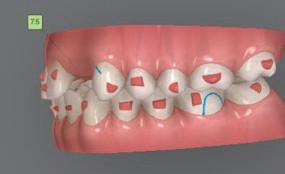

Dental Tribune Bulgarian Edition / октомври 2022 г.16 клиничен случай с алайнери Г орният латерален ре зец е вторият найчесто вродено липсващ зъб.1,2 Поради разполо жението му във видимата зона на усмивката лечение то на подобни случаи нала га мултидисциплинарен под ход, целящ отличен функцио нален и естетичен резултат. Налице са няколко лечебни мо далности, свързани с различ но разпределение на място то: първият вариант е орто донтско отваряне на място и възстановяване на липсва щия зъб с конструкция, под държана от съседните зъби3 или от имплант4, докато при втория подход разстоянията се затварят и премоларът заема мястото на канина.5 Изборът на лечебен подход трябва да бъде направен съв местно от зъболекар и паци ент въз основа на очакванията на последния и предвиди мостта на лечението. Множе ство фактори влияят върху това решение, като напри мер типа малоклузия, размера, формата и цвета на кучеш ките зъби6, оклузалните вза имоотношения (овърджет и овърбайт), лицевия профил, дължината на зъбната дъга и несъответствията в разме ра на зъбите.7 В настоящата публикация се разглежда случаят на жена в зряла възраст с вродена лип са на горен ляв латерален резец. Бяха приложени про зрачни алайнери за отваряне на място за единичен им плант и бяха постигна ти функционална оклузия и отлична естетика. ПРЕДСТАВЯНЕ НА СЛУЧАЯ Диагноза Пациентката бе на 32 годи ни, когато лечението започна, и първоначалното ѝ състоя ние бе следното (фиг. 1–3): липсващ горен ляв латерален резец; клас II, подклас I малоклузия; отклонение на горната сре динна линия вляво; Доклад на клиничен случай ЛЕЧЕНИЕ С АЛАЙНЕРИ НА ПАЦИЕНТ С АГЕНЕЗИЯ НА ЛАТЕРАЛЕН РЕЗЕЦ Д-р Iro Eleftheriadi и д-р Christodoulos Laspos, Гърция и Кипър Фиг. 1a–h Предоперативни лицеви и интраорални снимки. Фиг. 2a–e Дигитални модели преди началото на лечението. Фиг. 3 Панорамна снимка преди лечението. Фиг. 1a Фиг. 1d Фиг. 1f Фиг. 2a Фиг. 2d Фиг. 2b Фиг. 2e Фиг. 3 Фиг. 2c Фиг. 1b Фиг. 1e Фиг. 1g Фиг. 1h Фиг. 1c

Dental Tribune Bulgarian Edition / октомври 2022 г. 17клиничен случай с алайнери леко струпване в долната че люст; несъответствие по Болтън (мандибуларен излишък от 3.06 мм във фронталната зона и общо 1.47 мм); издължено лице с лицева аси метрия; конвексен профил с ретруди рана долна челюст и проми нентен нос. На мястото на зъб #46 бе на лице имплант, а зъби #16 и 26 са ендодонтски лекувани. Тези зъби бяха асимптоматич ни, затова бе взето решение да се прави релечение само при нужда. Мъдреците липсваха. Анализът на телерентгеногра фията (фиг. 4) показа ретрог натна мандибула (SNB: 74.2°) и нормална инклинация на резците както в

Цели на лечението и лечебен план Целите на лечението бяха следните: нивелиране и подреждане на зъбите и в двете зъбни дъги; отваряне на пространство за липсващия латерален резец; коригиране на отношенията при канините и моларите до клас I; и корекция на отклонението на срединната линия. Лечебният план включваше: корекция на отношенията при кучешките зъби и мола рите до клас I с дистализира не на максилата; отваряне на пространство в областта на #22 за поставя не на единичен имплант; корекция на срединната ли ния; и създаване на място за раз ширяване на зъб #12 и апрок симална редукция в долната челюст с цел подобряване на несъответствието по Болтън и осигуряване на подобра оклузия. Изпълнение на лечебния план Този случай бе изпълнен със системата за алайнери Invisalign (Align Technology). Одобреният първоначален лечебен план предвиждаше 49 алайне ра с дистализиране на задни те горни зъби до клас I (прибли зително с около 3.5 мм; фиг. 5). За бъдещия имплант в областта на липсващия латерал бе планирано пространство от 6.5 мм, докато във фронталния сегмент на долната челюст бе предвидена апроксимална редук ция. В дясната страна бутон за ластици клас II бе поставен на зъб #47 вместо на зъб #46, за да не се увреди короната на импланта. Понеже пациентката жи вееше в чужбина,

следните казуси: недобра оклу зия в дисталните зони по вре ме на дистализирането на гор ната челюст и накланяне на зъб #21 (фиг. 7). Последното се дължи на липсата на компози тен атачмънт на този зъб, каквото не бе зададено в пър Фиг. 4 Телерентгенография и цефалометричен анализ преди началото на лечението. Фиг. 5a–e Одобреният първоначален лечебен план. Фиг. 6a–h Снимки по време на лечението, показващи нуждата от внасяне на някои корекции. Фиг. 4 Фиг. 5a Фиг. 5d Фиг. 6a Фиг. 6d Фиг. 6f Фиг. 6b Фиг. 6e Фиг. 6g Фиг. 6h Фиг. 6c Фиг. 5e Фиг. 5b Фиг. 5c

Dental Tribune Bulgarian Edition / октомври 2022 г.18 воначалния план. Тези пробле ми бяха адресирани чрез допъл нителна поръчка на алайнери с торк контрол и зададено екст рудиране на задните зъби с цел установяване на добри оклузал ни контакти в дисталните об ласти, като бяха предвидени и оптимизирани атачмънти с контрол над корените за корекция на ангулацията на макси ларните резци (фиг. 8). Резултати от лечението Панорамната рентгено графия след ортодонтското лечение показа благоприятна паралелна позиция на съседни те зъби, подходяща за поставя не на имплант в областта на #22, както и конвергенция на ко рените на зъби #44 и 45 (фиг. 9), но преценихме, че няма да от деляме допълнително лечебно време за коригирането ѝ поради факта, че пациентката бе мно го доволна от постигнатия до момента резултат. След при ключване на лечението бяха постигнати отлични взаимо отношения клас I при мола рите и канините, а срединни

съвпадаха. Върху им

планта бе поставена временна коронка (фиг. 10 и 11), докато бъде изготвена окончателна та. Бе постигнат отличен кра ен резултат. Меките тъка ни около импланта напълно заздравяха, което доприне се за перфектната хармония между бяла и розова естетика (фиг. 12–15).